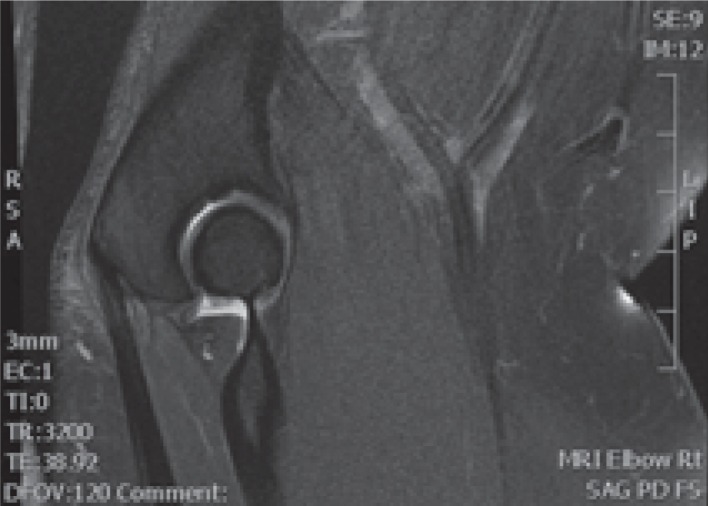

Plain radiography is unlikely to aid significantly in the diagnosis but may show some osseous reaction to the radial tuberosity [31]. MRI and ultrasonography remain the investigations of choice. MRI findings (Fig. 2) include an abnormal signal intensity on fluid sensitive images within the tendon at its insertion, bicipitoradial bursitis, and focal marrow oedema in the radial tuberosity [33]. Performing the MRI with the patient lying prone, the shoulder abducted, elbow flexed to 90° and fully supinated (‘FABS’ position) allows visualization of the whole distal biceps tendon on a single image [40]. The sensitivity and specificity for diagnosing partial tears of the distal biceps tendon using conventional MRI (i.e. not FABS position) is 59.1% and 100%, respectively [41]. No studies have assessed the sensitivity and specificity in the FABS position.

Fig. 2.

Magnetic resonance imaging showing a normal and tendinopathic distal biceps tendon.